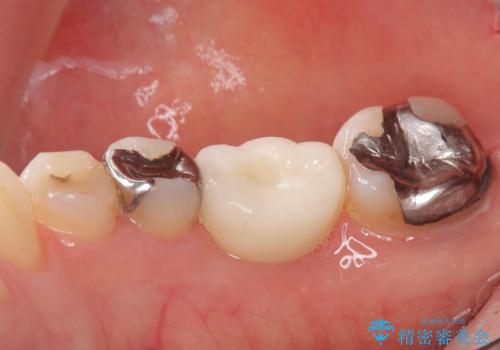

骨の量は十分あったため、比較的短期間で治療は終了しました。

安定した咬み合わせとなり、痛みもなく安心して噛めるようになりました。